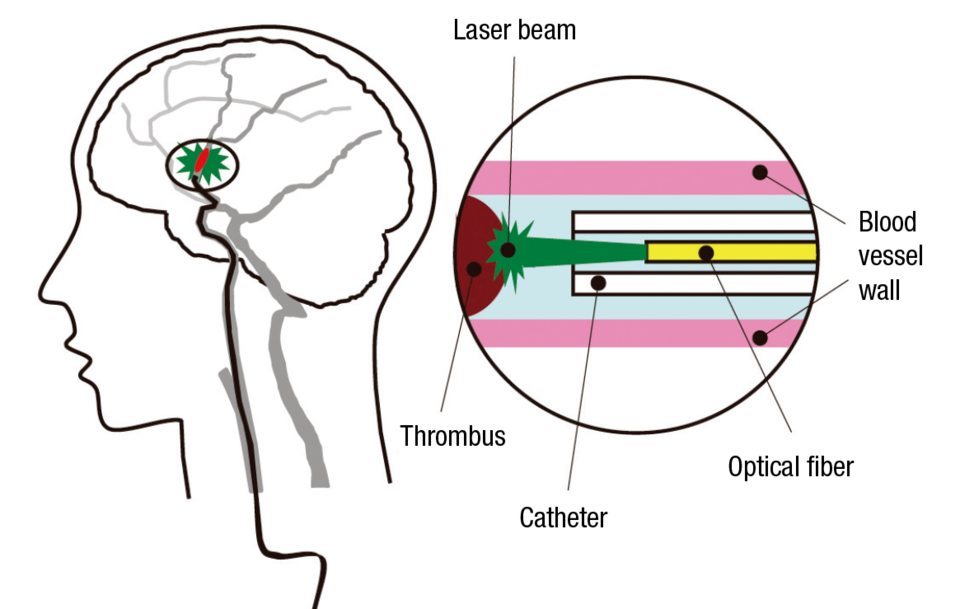

Hamamatsu Photonics has also developed many world-class products in the field of lasers, in which it started R&D activities in the 1990s. Recently it became the first in the world to develop a laser thrombolysis technology for treatment of cerebral thrombi—blood clots in the brain that cause strokes—which works as follows: A catheter encasing an optical fiber is inserted via a femoral artery and extended to the location of the thrombus, and a green laser beam at a wavelength of 532 nanometers is directed at the site. At this wavelength, the beam is not absorbed by the blood vessel wall but affects only the thrombus, which it dissolves with almost no risk of damage to the blood vessel walls. Since the tip of the catheter is thin, with a diameter of only 0.8 millimeters, and flexible, it can be used for treatment in blood vessels of around 1 mm in diameter, which are hard to treat with existing devices for suction-purpose catheterization. In this way it offers hopes for expanding the scope of cases that can be treated.